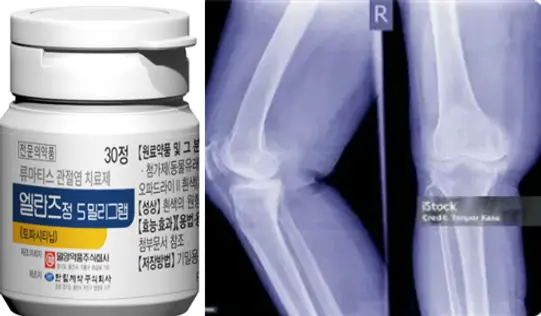

▲일양약품 신제품 류마티스 관절염 치료제 ‘엘란즈정 5밀리그램’과 관절염 사진.

일양약품이 류마티스 관절염 치료제 ‘엘란즈정 5밀리그램’을 출시했다.

24일 익양약품에 따르면 엘란즈정은 토파시티닙 성분의 경구용 치료제로, 류마티스 관절염 약물치료에 사용되는 표적 합성 항류마티스제(tsDMARD)에 해당한다.